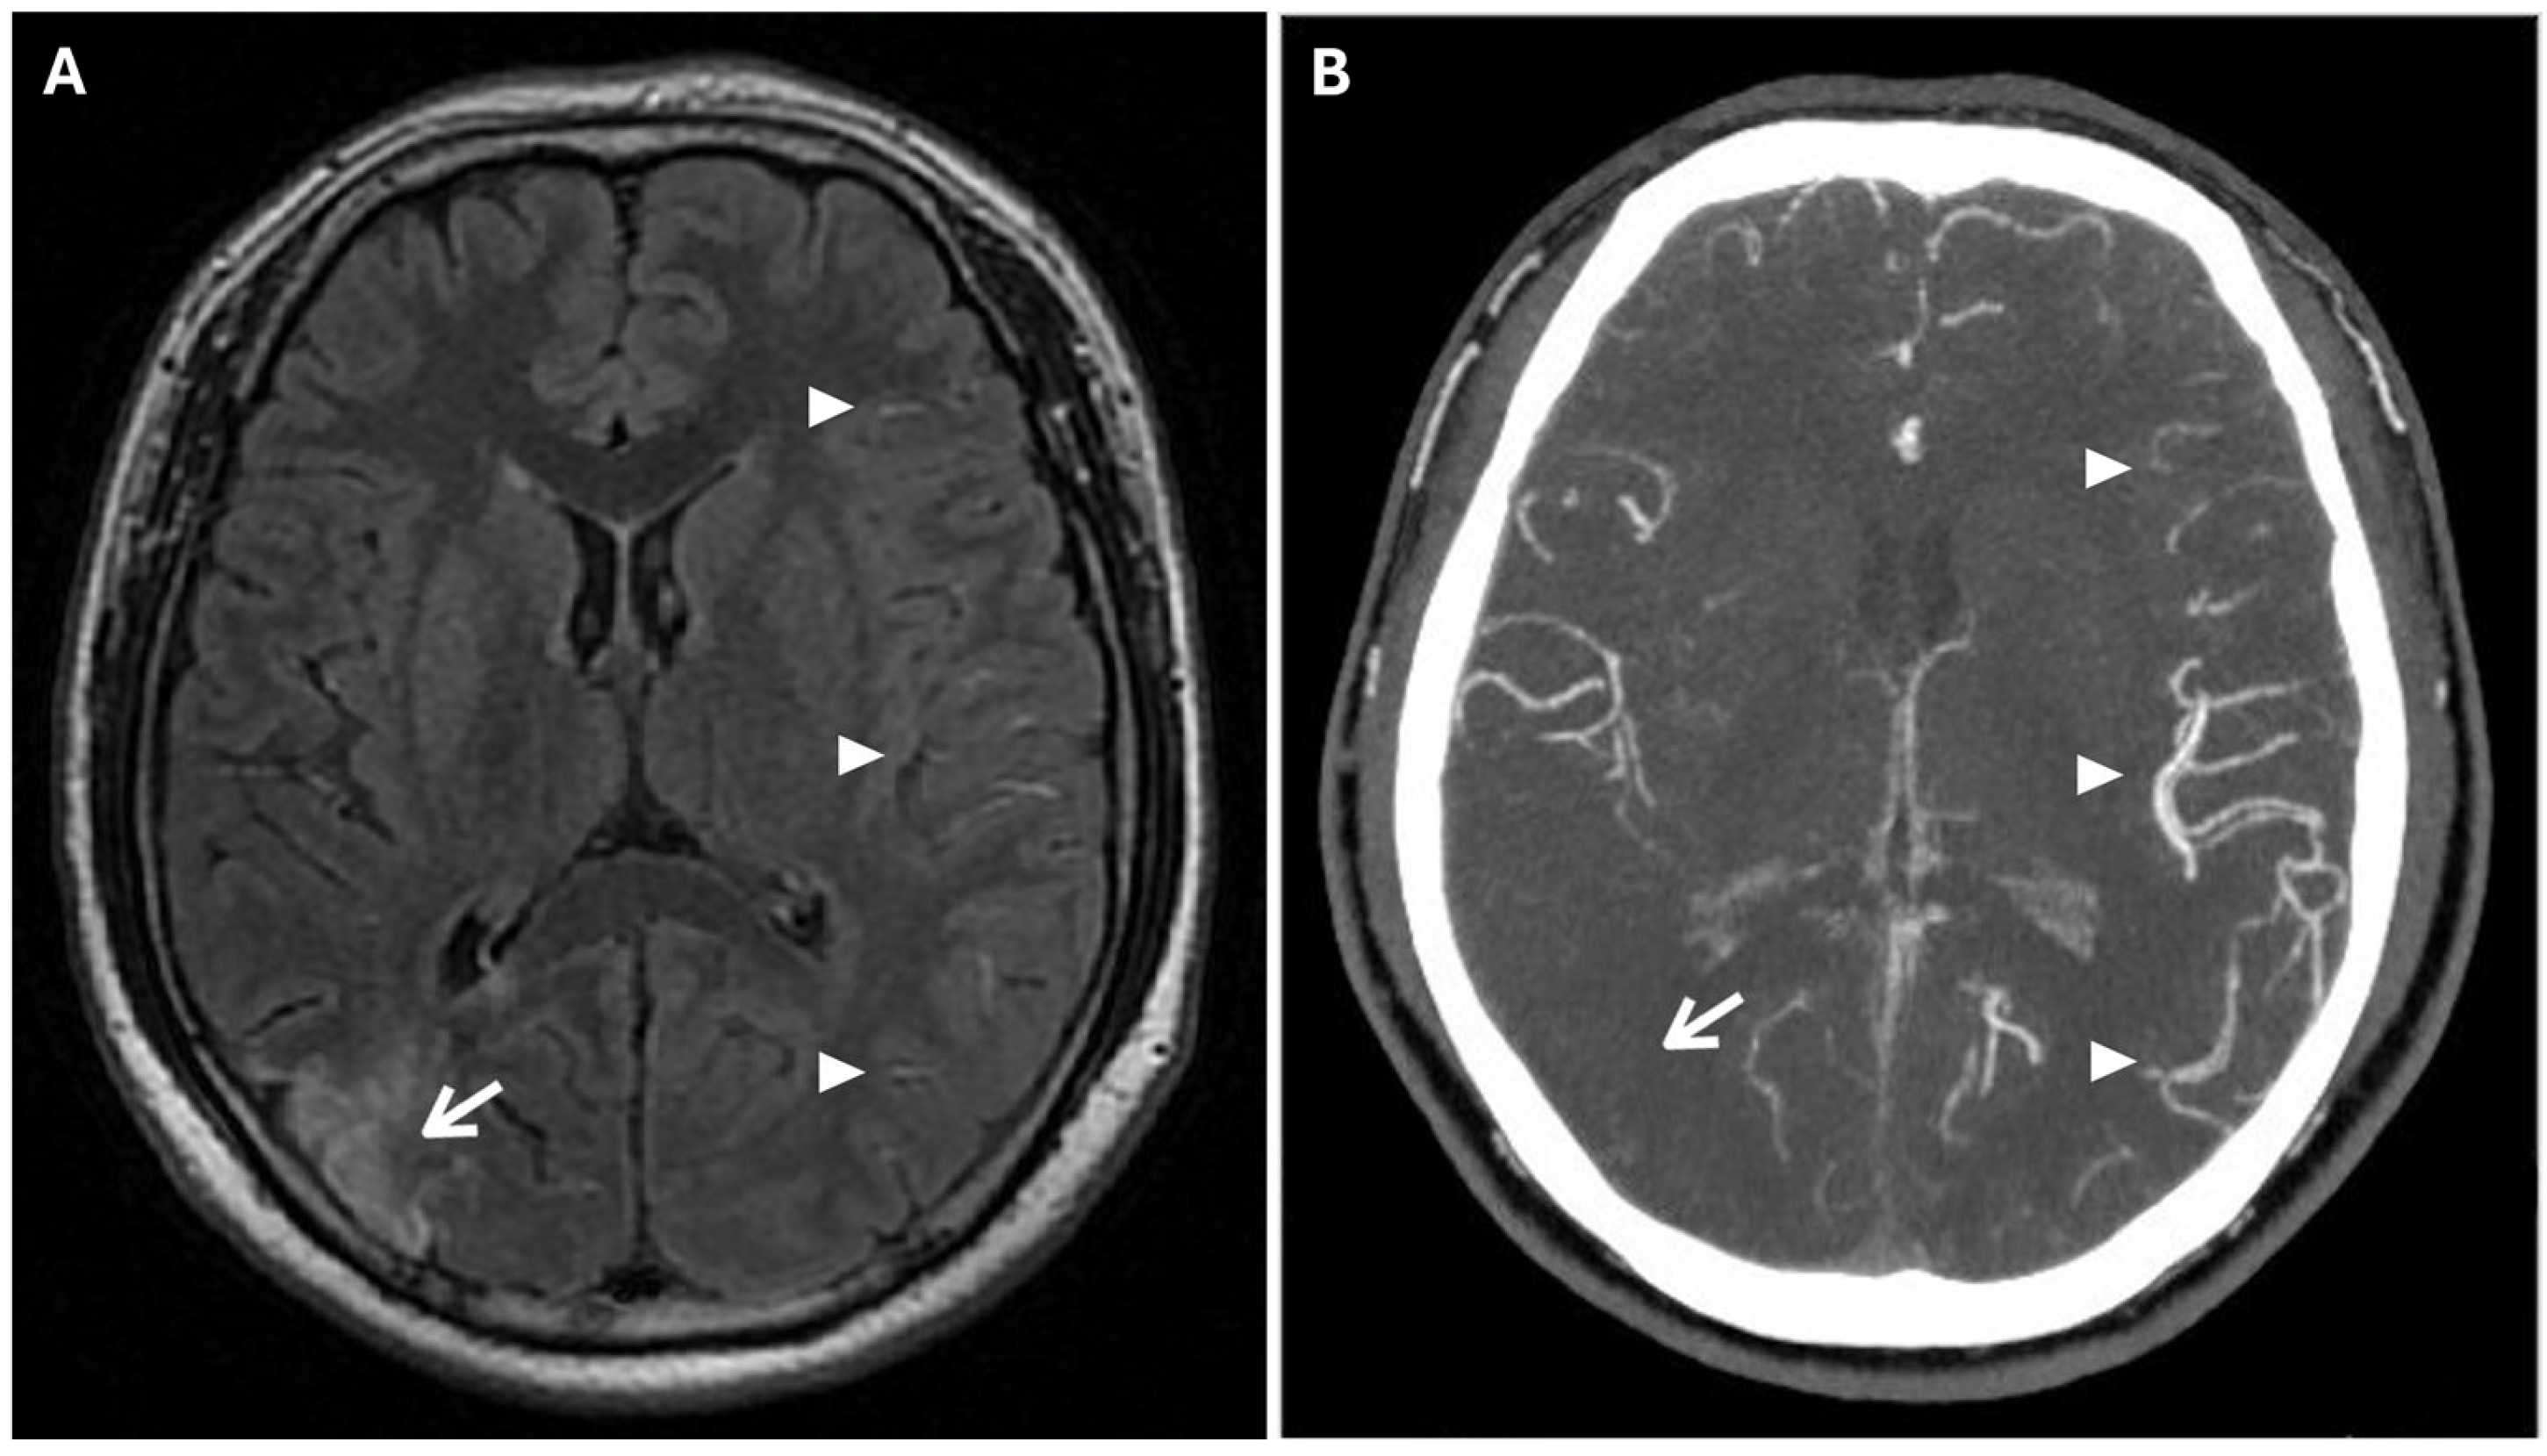

Another phenomenon that can be observed on FLAIR sequences is the “medullary streak” sign, which is characterized by a hyperintense streak oriented perpendicularly to the lateral ventricle (“periventricular medullary veins/FLAIR hyperintense streaks”); despite its etiology remaining ambiguous, the condition has been associated with ischemia and could represent collateral vasculature, stagnated cerebrospinal fluid, or vasogenic edema (Figure 7).

Figure 7. Axial (A) and coronal (B) 3d FLAIR sequences show a hyperintense streak area oriented perpendicularly to the right lateral ventricle (white arrows), representing the “medullary streak” sign. Note the right parietal subacute ischemic lesion (white arrowhead).

Approximately half of adult patients with MMD may develop intracranial hemorrhage. The location of the hemorrhage can be subarachnoid, intraventricular, or intraparenchymal, more often within the basal ganglia [3]. Microbleeds can be detected through the use of gradient echo T2* sequences or susceptibility-weighted imaging (SWI), the latter being a 3D gradient-echo sequence with an increased spatial resolution and higher sensitivity to these alterations. Microbleeds may be associated with leakage from dilated and fragile collateral vessels, such as the anterior choroidal or posterior communicating arteries. These alterations also have a prognostic value, as they indicate an increased risk for intraventricular hemorrhage, particularly if located in the periventricular area [2]. In fact, rupture of prominent and fragile anterior choroidal arteries leads to intraventricular hemorrhage, as often observed in MMD [22]. Furthermore, SWI and FFE sequences can detect prominent medullary veins, identifying hypointense blooming artifacts within multiple intracranial blood vessels (“prominent vessel sign”). This sign reflects an increased concentration of paramagnetic deoxyhemoglobin in cortical veins (referred to as the “cortical vein sign”), subependymal and medullary veins (referred to as the “brush sign”) (Figure 8), and it is associated with an increased risk of infarction, low cerebral blood flow (CBF), and low cerebrovascular reactivity [17,23].

Figure 8. (A) Axial FFE sequence shows subependymal and medullary veins bilaterally, representing the “prominent vessel sign” (white arrowheads). (B) Magnification of the previous image illustrates deep medullary veins on the left hemisphere (wavy black lines).